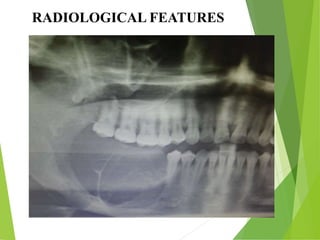

RADIOLOGICAL FEATURES

RADIOGRAPHIC FINDINGS

• Ameloblastomas are osteolytic & present as

unilocular or multilocular.

• Well circumscribed by bony radiopaque borders

• Margins are usually well defined & sclerotic

• Root resorption & tooth displacement.

• Displacement of the neurovascular bundle

• Cortex shows thinning and often severe expansion

• Involvement of the antrum is seen as an opacification.